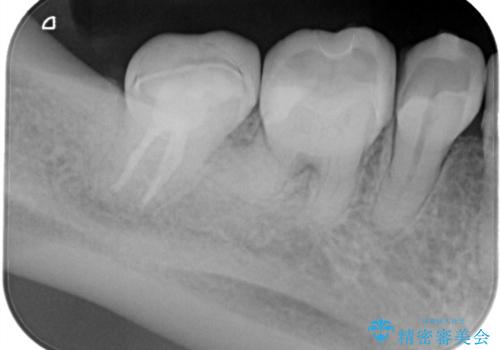

定期検診にて膿の出口を見つけた。精密根管治療

- 定期検診にて膿の出口を見つけたことを主訴に来院されました。

検査の結果、診断を歯髄壊死、症候性根尖性歯周炎とし抜髄を行っております。

根管充填はCWCTにて行なっています。